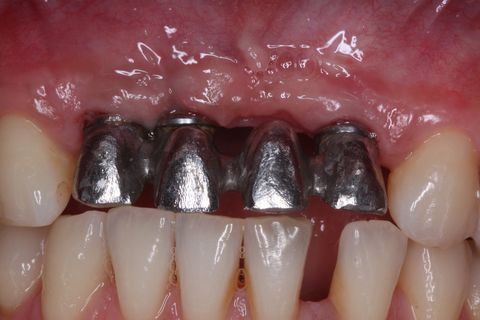

Minipilares instalados. Nota-se apenas 3 minipilares pois um dos implantes foi perdido. Instalamos um novo implante que também foi perdido. Optamos em manter apenas 3 implantes e finalizar a prótese fixa parafusada.

Prova da Subestrutura metálica